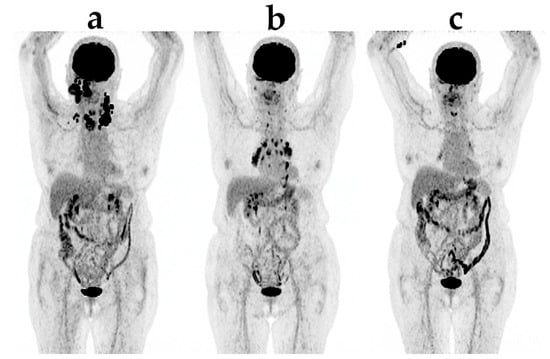

Figure 1. Example of early pseudoprogression in a patient with malignant melanoma: (a) initial Positron Emission Tomography/Computer Tomography with 18F-Fluorodeoxyglucose; (b) first evaluation after four series of ipilimumab shows multiple new foci in the liver and the bones with highly increased LDH (lactate dehydrogenase); and (c) subsequent scans after completion of treatment showing complete disappearance of both new foci and the primary lesions.

Pseudoprogression is seen on both CT and FDG-PET as a prematurely diagnoses of progressive disease (Figure 1). The apparent progression is both caused by the invasion of immune cells into the tumors causing the tumors to increase in size and to accumulate FDG and the continued tumor growth during therapy, until a sufficient immune response is developed [24]. Using irRC, two types of pseudoprogression has been described: (1) early pseudoprogression with more than 25% increase in tumor burden at 12 weeks and not confirmed as PD at the next assessment; and (2) late pseudoprogression with more than 25% increase in tumor burden after 12 weeks that was not confirmed as PD at the next assessment. Early pseudoprogression is probably most common. In the new iRECIST, both scenarios are classified as iUPD, and a patient can have several instances of iUPD, but not iCPD, before response (iCR, iPR or iSD) [27]. It is important to stress that pseudoprogression is a relatively rare phenomenon seen only in 3%–10% of the patients and that it is a retrospective diagnosis [20,24].